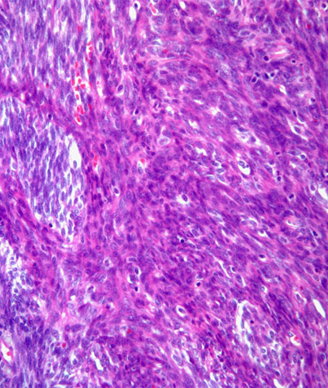

Surgery is the mainstay of treatment for localized soft-tissue sarcoma (STS). It consists primarily of resection of the tumor along with a cuff of surrounding healthy tissue. In limb and trunk wall sarcomas, this basically implies resection of the surrounding soft tissues, which are mainly muscles, subcutaneous fat, and skin.[1] In the retroperitoneum, this necessarily should imply resection of adjacent viscera, even when they are not overtly involved.[2] This is the only way to avoid/minimize the presence of tumor cells at the cut surface (ie, positive microscopic surgical margins). Positive microscopic surgical margins are associated with a higher risk of local failure, distant metastases, and death.[3-6] Moreover, for STS located at critical sites, such as retroperitoneal sarcoma (RPS), positive surgical margins may have a direct impact on survival, favoring the development of inoperable local recurrences.[7] Indeed, unlike with STS arising in the extremities and trunk wall, local control in RPS poses a significant challenge and remains the leading cause of death, particularly in patients with low- to intermediate-grade tumors-roughly 75% of all cases.[8-13] Extending the resection to adjacent uninvolved viscera for primary RPS is the only way to minimize the presence of microscopic surgical margins and hence maximize the chance of cure. In essence, this strategy should often include ipsilateral nephrectomy and colectomy; locoregional peritonectomy and myomectomy (partial/total) of the muscle of the lateral/posterior abdominal wall (usually the psoas) (see Figure); splenectomy and left pancreatectomy, for tumors located on the left upper side; occasionally pancreaticoduodenectomy or hepatectomy, for tumors located on the right side; and vascular and bone resection only if vessels/bone are overtly infiltrated.[2]